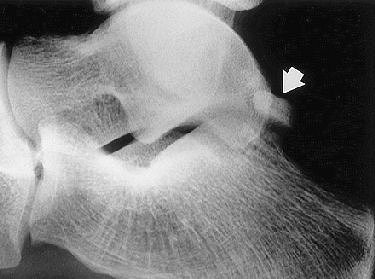

The group performed MR exams in seven patients with indeterminate pain in the posterior ankle. One of these patients was a 20-year-old soccer player who had complained of pain in the posterior ankle, which started two weeks after a game.

According to the soccer player's results, MR depicted bone marrow edema of the os trigonum, lateral talar tubercle, and subtalar synovitis. No other osseous anomalies and no tibiotalar synovitis or flexor hallicus longus (FHL) tenosynovitis were seen. The PAI diagnosis was established on the basis of MR findings, the group stressed. The patient underwent successful conservative treatment.

| PAI syndrome in a 20-year-old male soccer player. Above, lateral radiograph of the right ankle demonstrates a well-defined os trigonum (arrow). Middle, sagittal T1-weighted image (366/14) shows area of low signal intensity (arrow) within the os trigonum. Below, sagittal, fast spin-echo inversion-recovery image (4,000/69; inversion time, 130 msec) medial to middle image demonstrates bone marrow high signal intensity (arrows) in the posterior talus, consistent with a bone contusion. |

| Figure 1abc. Bureau NJ, Cardinal E, Holden R, Aubin B, "Posterior ankle impingement syndrome: MR imaging findings in seven patients." Radiology 2000; 215:497-503. |

Also in all patients, MR depicted low signal intensity of the os trigonum and/or lateral talar tubercle on T1-weighted images, as well as high signal intensity on fat-suppressed T2-weighted imaging. These signs were consistent with bone marrow edema. A major advantage that MR has over x-ray or CT is the ability to depict bone contusions or occult fractures as their presence may influence treatment, they added.